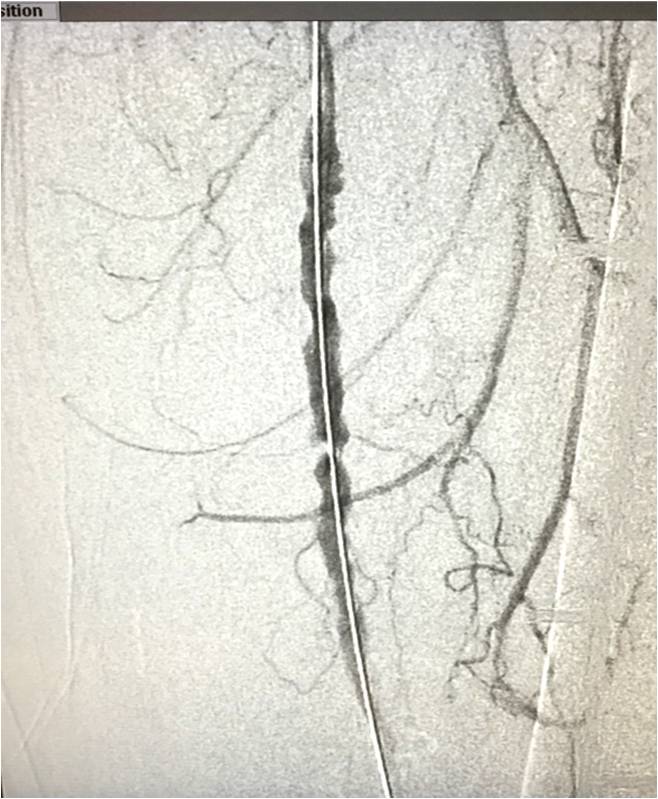

2015年10月30日,彩神在线网信彩票-彩神通免费版下载-彩神8争霸vlll-彩神购彩购彩大厅-彩神软件陆立根免费版-彩神ll争霸3-彩神ll彩神8-彩神ll争霸彩票-拼搏在线彩神网网页版科技GoldenFlow™外周支架的FIM(First in Man)临床实验的首例入组在香港威尔斯亲王医院完成,此为该支架系统全球首次植入人体。此次共入组2例病人,使用了3个GoldenFlow™外周支架。手术过程顺利,支架定位准确、释放平稳。

图1 病变位置 图2 植入GoldenFlow™外周支架